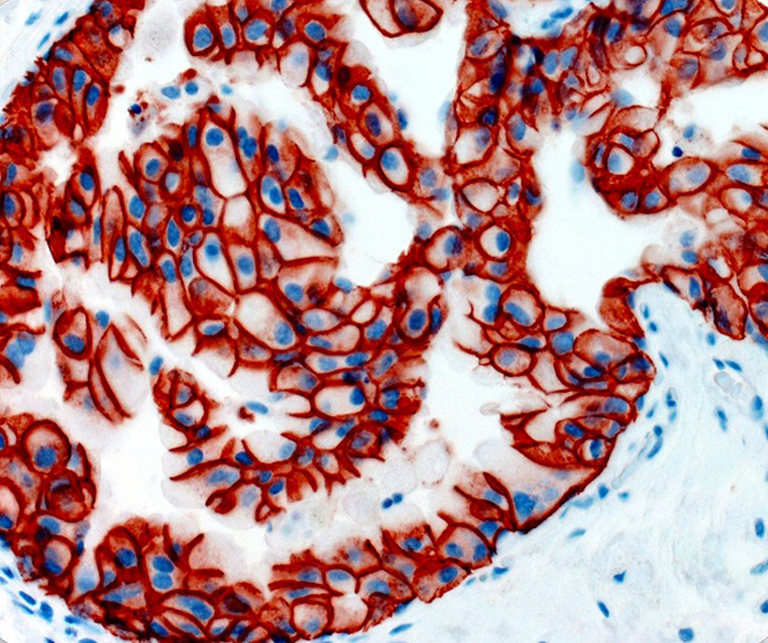

Vascular Pathology

Gastrointestinal (GI) Pathology

General Marker

Breast Pathology

Endocrine Pathology

Gynecological Pathology

Neuropathology

Infection Markers

Lung Pathology

Urinary Tract Pathology

Transplantation Pathology

Soft Tissue Pathology

Hematopathology